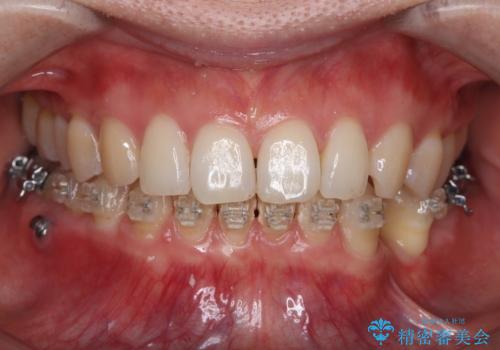

- ワイヤー矯正中の患者様です。

今回は汚れを染め出しクリーニングをしました。

ワイヤーの装置周りは歯ブラシが当てにくいので、歯石や歯垢などが残り歯周病・虫歯になりやすいです。そのため定期的なクリーニングをおすすめしております。